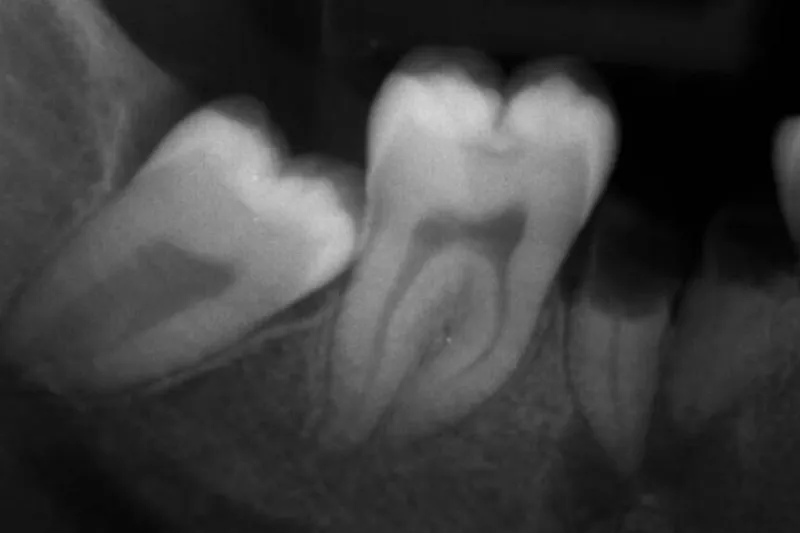

I studiet indgik 222 voksne personer, som alle deltog i et vedligeholdelsesprogram efter gennemført parodontalbehandling. Personerne havde ved undersøgelsesperiodens start 1.329 molarer, hvoraf godt halvdelen havde furkaturinvolvering af grad I, II eller III. Observationsperioden var mindst 10 år (12,4 ± 1,9 år).

I løbet af perioden mistede patienterne i alt 235 molarer, hvilket gav en overlevelsesrate på 82,3 %. Det er værd at bemærke, at kun 161 molarer (68,7 %) blev ekstraheret af parodontale årsager, mens de øvrige mistedes som følge af bl.a. caries, endodontiske tilstande og rodfrakturer.

Ved regressionsanalyse fandt man, at følgende patientrelaterede faktorer havde signifikant negativ indflydelse på overlevelsen af molarer: Alder > 50, hankøn, diabetes, rygning og manglende komplians. Tilsvarende negativ virkning blev påvist for en række odontologiske parametre: Gingival blødning, pochedybde ≥ 5 mm, furkaturinvolvering grad III samt manglende pulpavitalitet.